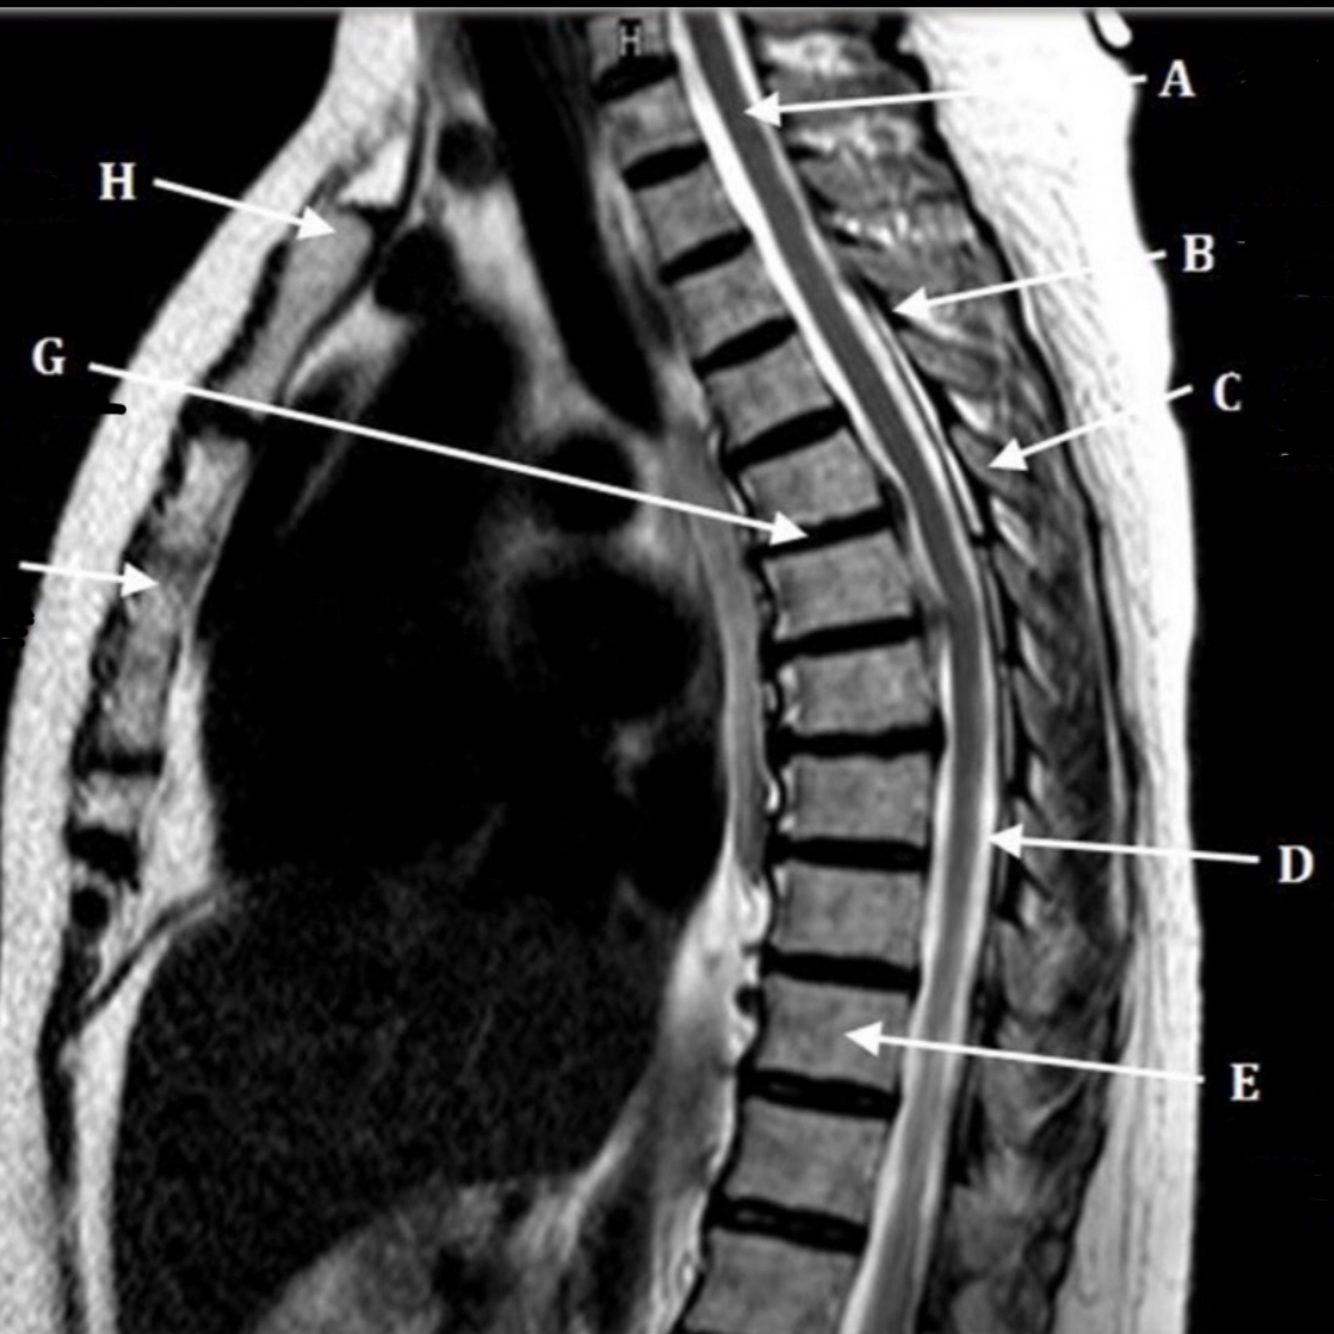

Q

CSF

SPINAL CORD

What is letter C?

LAMINA

What is letter D?

DORSAL NERVE ROOT

What is letter E?

VENTRAL NERVE ROOT

What is letter F?

VERTEBRAL BODY

What is letter G?

SPINOUS PROCESS

What is letter H?

TRANSVERSE PROCESS

What is letter J?

VERTEBRAL ARTERY